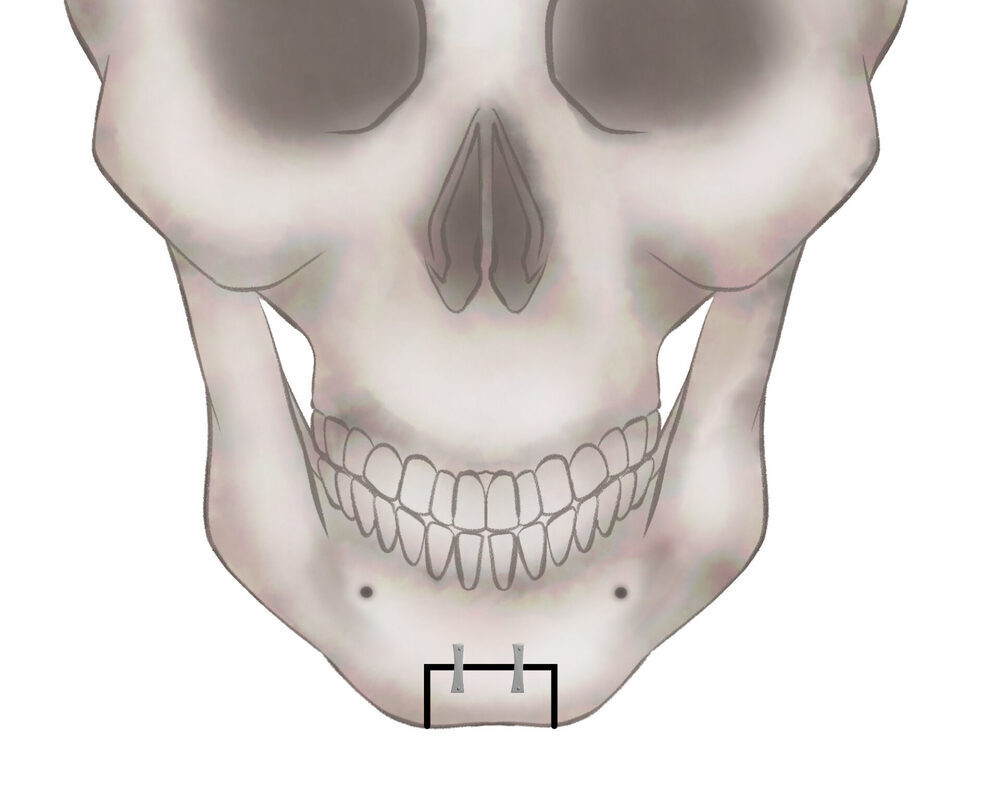

パターン1

骨を切る、もしくは削ります

パターン2

骨を切る、もしくは削ります

パターン3−1

骨を切る、もしくは削ります

パターン3−2

骨を移動してプレートで固定します